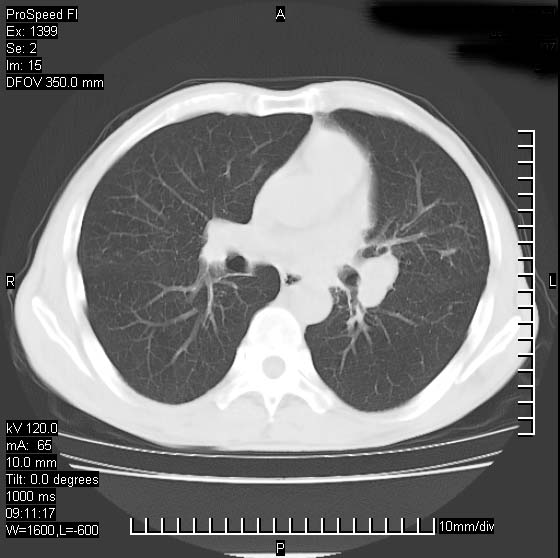

以下是引用卜一在2007-1-19 9:55:00的发言:[br]左肺沿胸膜下巨大肿块影,边缘呈分叶征,纵隔内见肿大淋巴结,右肺内另见一不规则结节影 .考虑:左肺周围性肺癌伴纵隔 右肺内转移.

以下是引用rgsyyf在2007-1-19 11:05:00的发言:[br]左肺上叶见形态不规则巨大软组织肿块影,边缘呈分叶征,纵隔内隆突下见肿大淋巴结,右肺内另见一不规则结节影 .考虑:左肺周围性肺癌伴纵隔即右肺内转移.